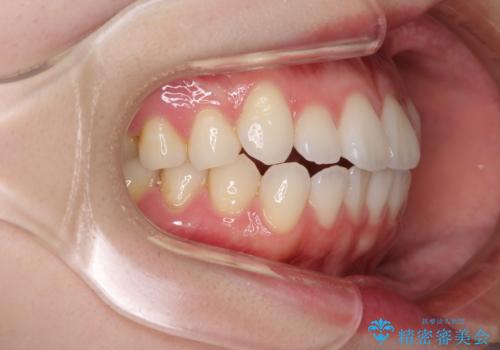

- 矯正治療の後戻りを気にして来院された患者様です。

後戻りは軽微でしたが、舌突出癖が認められ、初診時には上下前歯に舌がはまるスペースができていました。

舌突出癖の改善を行いながら、インビザライン・ライトにより矯正治療を行うこととしました。

舌突出癖の改善により上下前歯が接触するようになり、前歯でものを咬みきる必要のある食事がスムーズに行えるようになりました。